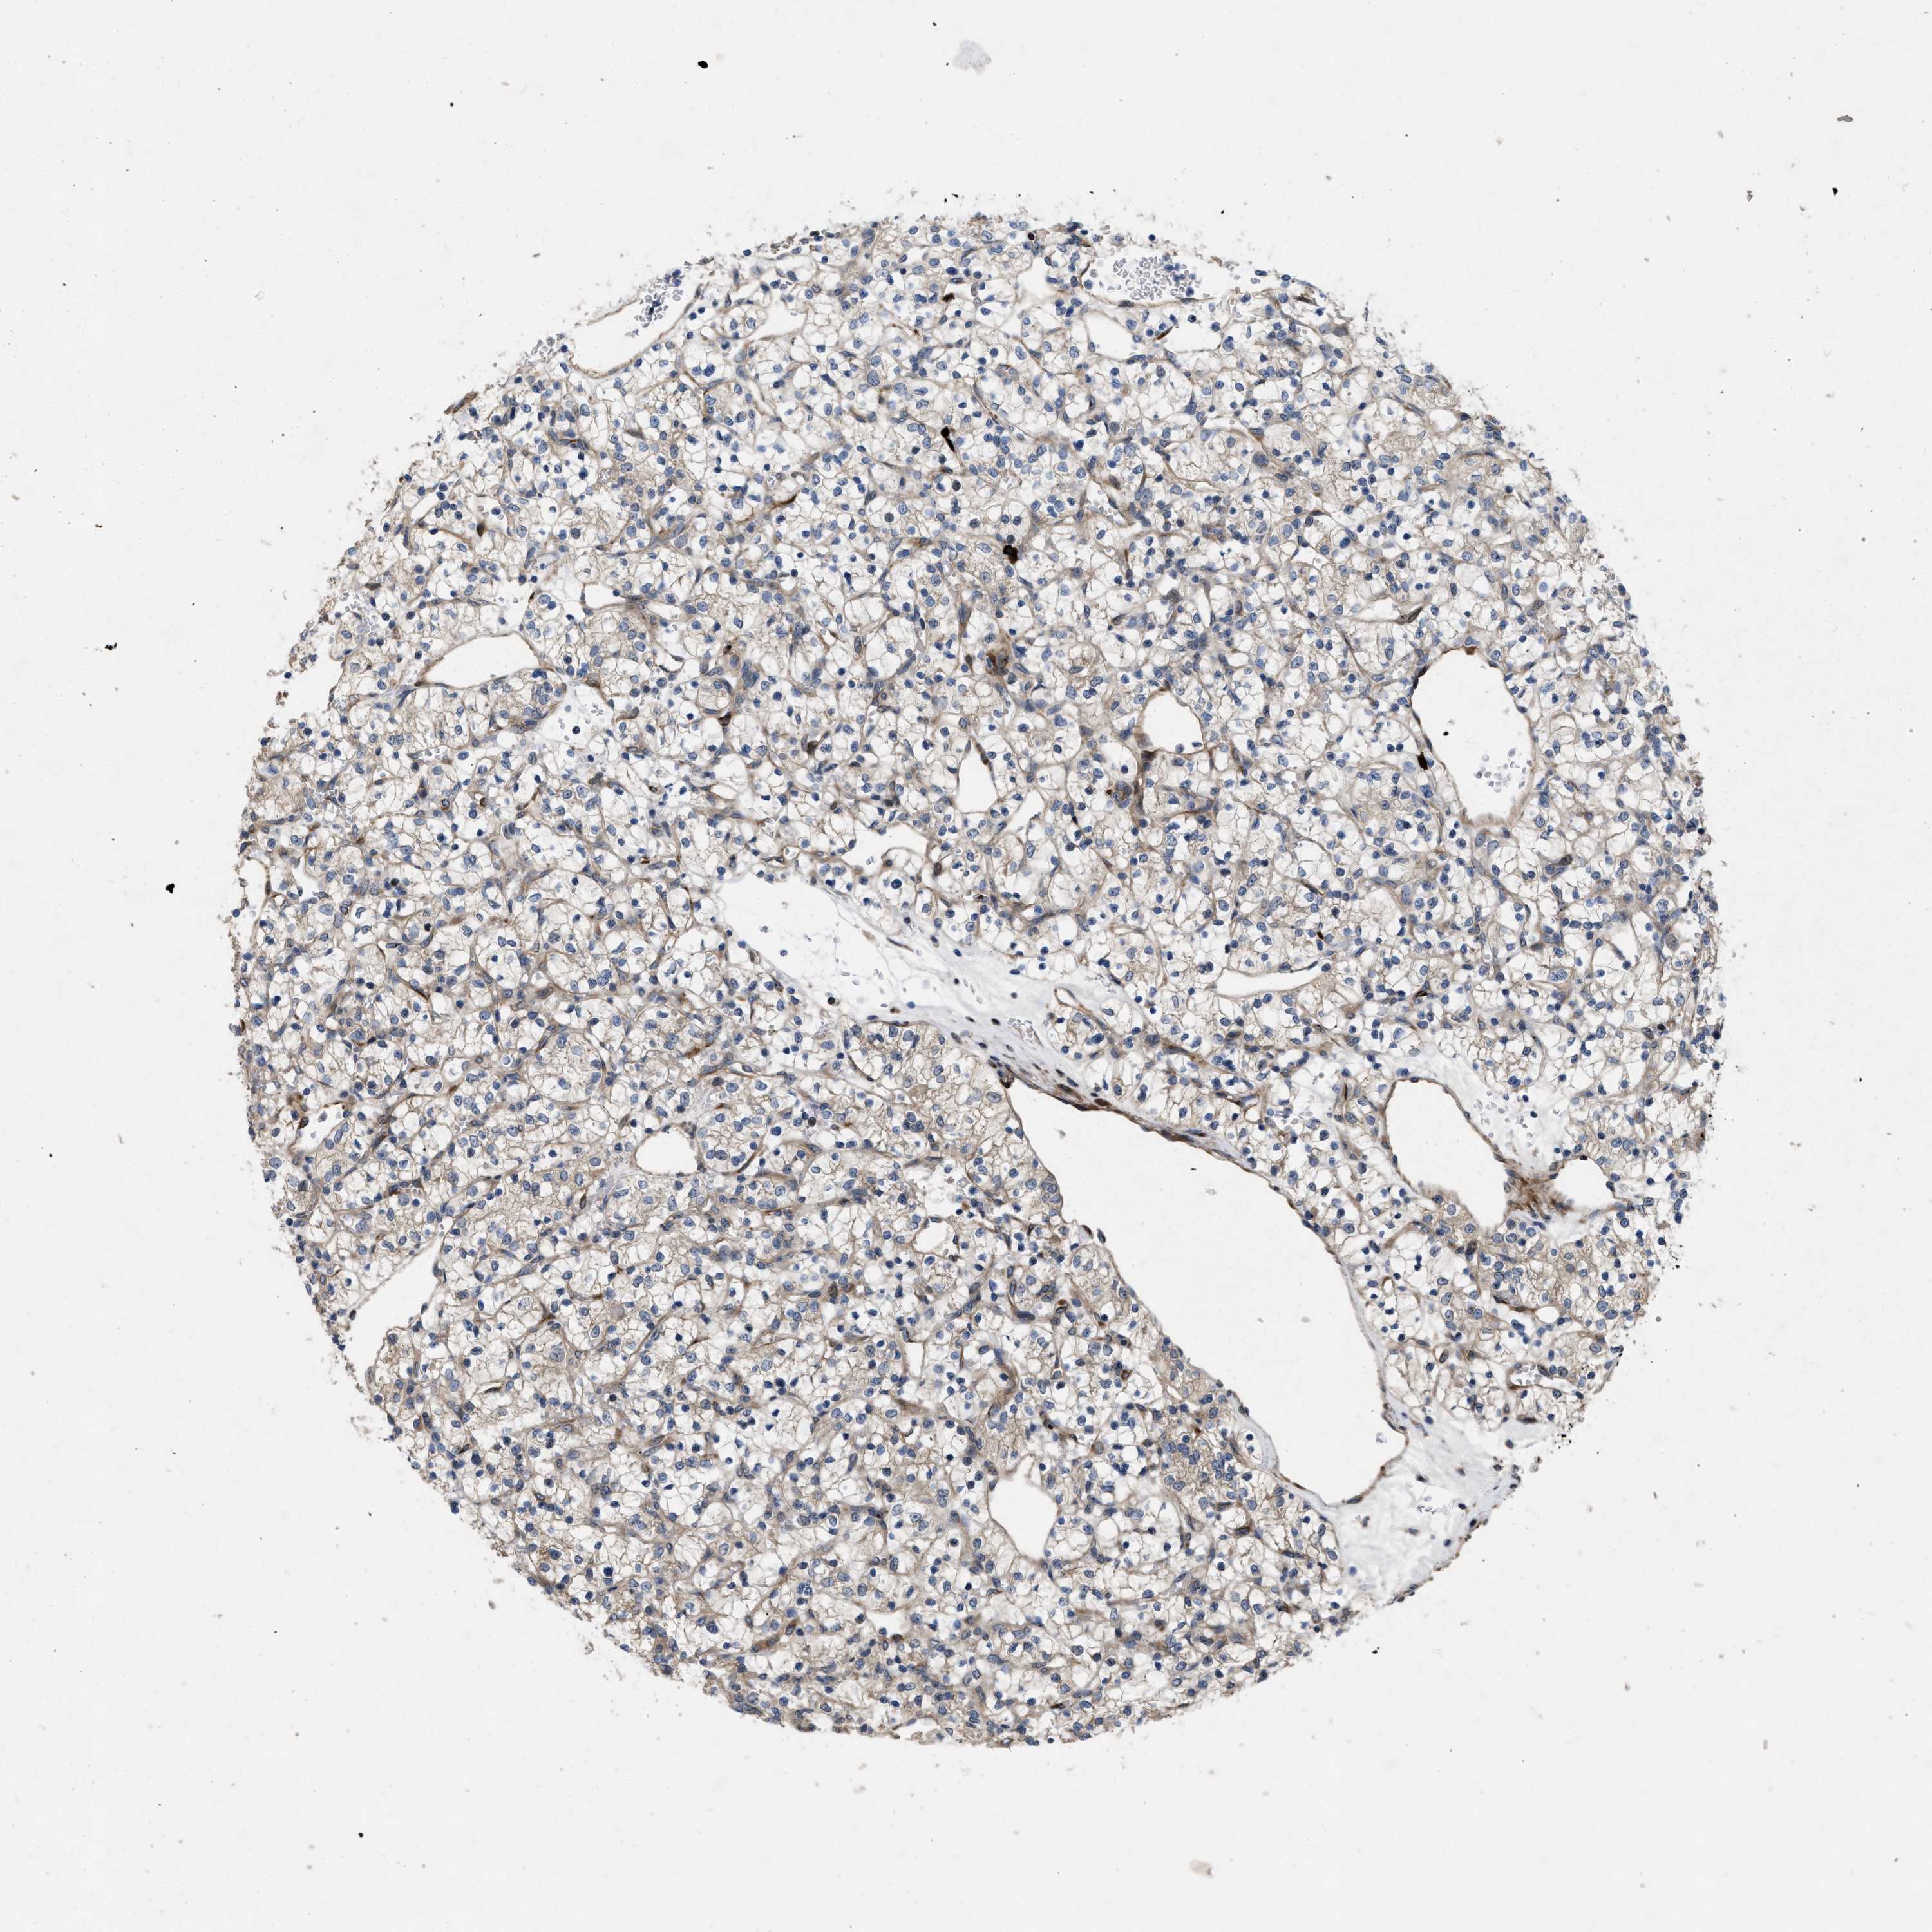

CANCER RENAL CANCER Show tissue menu

KICH TCGA KIRC TCGA KIRC VALIDATION KIRP TCGA PROTEIN RCC CPTAC PROTEIN EXPRESSION